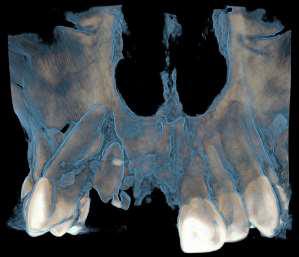

FRACTURA DE LOS MAXILARES

Las fracturas maxilares representan un desafío diagnóstico y terapéutico, ya que afectan a estructuras dentarias, óseas y senos paranasales.

La tomografía computada de haz cónico (CBCT) es el método de elección para valorar con precisión la extensión y ubicación de las fracturas debido a su capacidad de mostrar estructuras en tres dimensiones con alta definición y con diferentes filtros para una visibilidad adecuada a cada estructura

Desarrollo

En este caso se presenta una fractura maxilar y avulsión de pieza 1 1, la fractura de cortical vestibular va desde pieza 1 2 hasta 1 5 asociada a múltiples fracturas en cortical ósea vestibular de seno maxilar derecho. Enfatizando la importancia del diagnóstico tomográfico para este tipo de situaciones cuyo aporte en este caso particular es de alto valor diagnóstico.

Conclusión

La tomografía computada de haz cónico (CBCT) es indispensable para la evaluación de fracturas maxilofaciales complejas.

Las fracturas de los maxilares con compromiso de seno maxilar requieren de un diagnóstico oportuno para evitar complicaciones previas y durante la terapéutica

El abordaje terapéutico debe ser multidisciplinario y personalizado según las características individuales de cada caso, valorando la extensión de la lesión y el estado de las piezas dentarias afectadas.